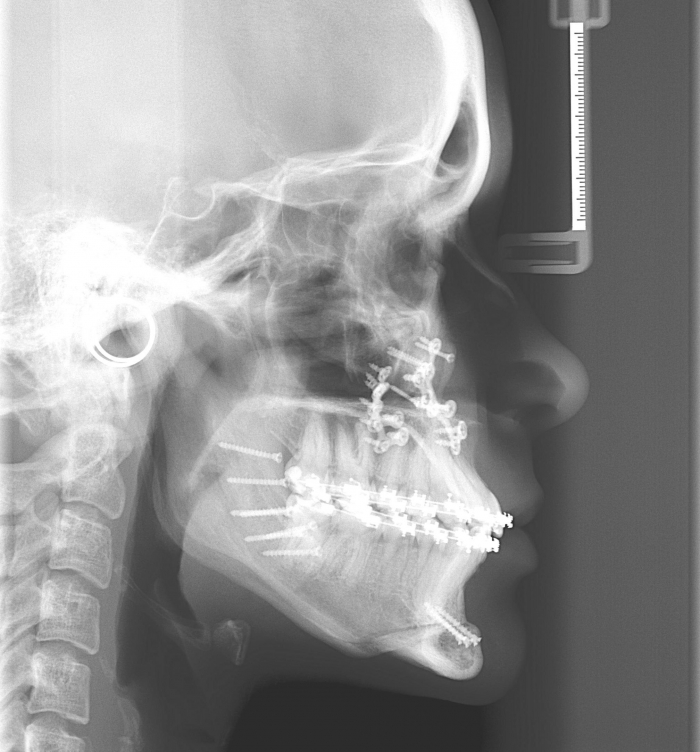

Telerradiografia após a cirurgia